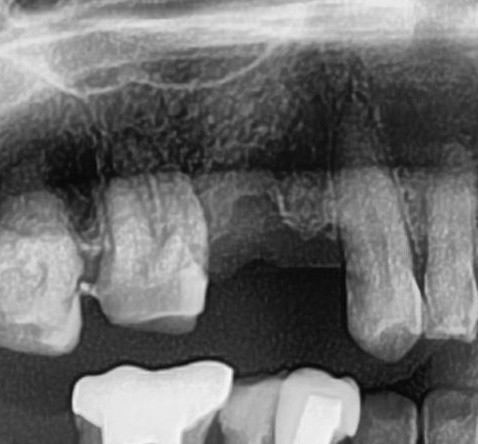

今回の患者様はインプラント植立を希望され、右上4番目・5番目の2本の植立が決まりました。

しっかりとインプラント埋め込まれた後は、動揺がないか、噛んだ時に当たらないかなどを確認して、最後にパノラマ写真を撮影して今回のオペは終了となりました。